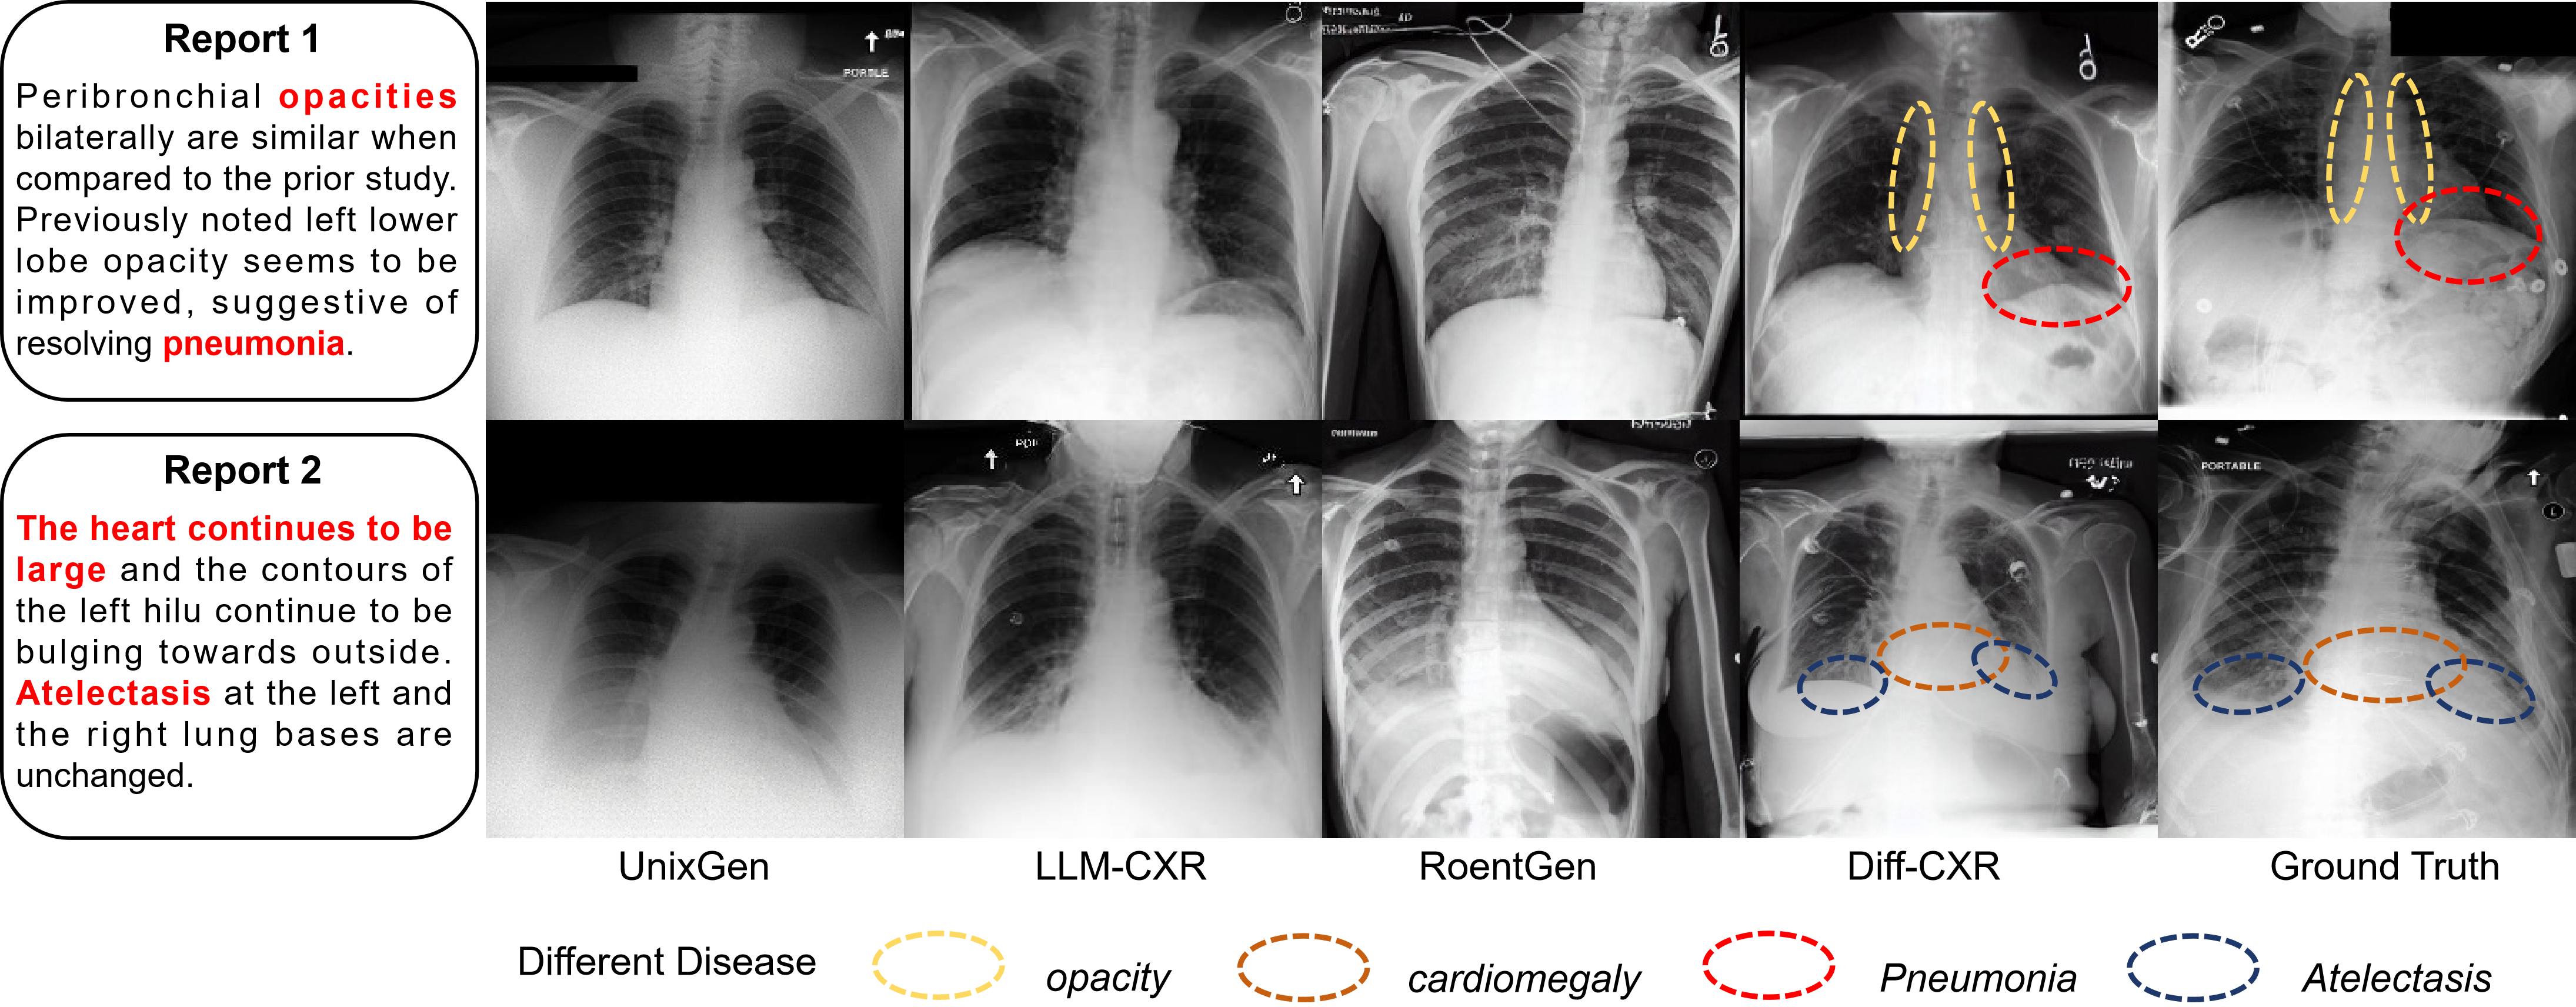

Experiments are conducted on MIMIC-CXR and IU-Xray to test both in-of-distribution and out-of-distribution performance. As shown in Table V, the AUC scores of images generated by Diff-CXR for nearly 11 common thorax diseases are consistently higher than those of LLM-CXR, indicating the best alignment between generated images and input reports. From Table IV, our Diff-CXR also surpasses LLM-CXR on the FID score by 9.770 and 9.829, respectively, proving the superiority of Diff-CXR in vision fidelity. As shown in Fig. 9, related disease representations are highlighted in images generated by Diff-CXR and the ground truth. Obviously, images generated by Diff-CXR share the similar disease imaging characteristics with the ground truth, underscoring the superiority of our method. Furthermore, our Diff-CXR demonstrates excellent generalizability towards unseen text with different distributions. Compared to LLM-CXR in IU-Xray, our Diff-CXR consistently delivers commendable results with an improvement of 56.4% and 23.8% in mAUC and FID score, respectively.